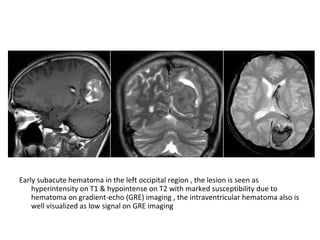

9-Hemorrhage :

-Hemorrhagic transformation is a little variably

used and collectively refers to two different

processes which have different incidence ,

appearance and prognostic implications ,

these are :

a) Petechial hemorrhage

b) Intracerebral hematoma

b) In the case of secondary hematomas :

-The radiographic features on both CT and MRI are

merely a summation of the features of a ischemic

infarct with superimposed cerebral hemorrhage

-The amount of hemorrhage relative the size of the

infarct can vary widely but usually it is possible to

identify significant areas of the brain which are

infarcted but not hemorrhagic

-This may not be the case if the hemorrhage is large

and the underlying infarct small

-By the time secondary hematomas form , the

underlying infarct should be easily seen

and will appear as a region of low attenuation

involving both the white matter and the

overlying cortex

-Hemorrhage is often patchy , scattered

throughout the infarcted tissue and usually

represents only a small component of the

abnormal tissue

T1 , Hemorrhagic transformation is detected as areas of increased

signal intensity , the gyral pattern of increased signal intensity may

also represent cortical laminar necrosis